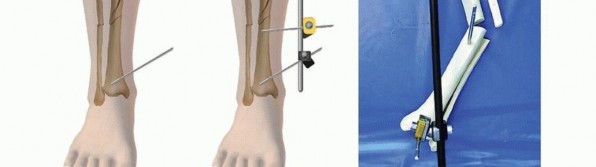

Ankle-Spanning Fixator for Tibial Pilon Fracture Two Schanz pins are placed into the midshaft tibial region ( TECH FIG 6). Avoid any compromised soft tissues and possible fracture extension if spanning the ankle for a severe pilon fracture with shaft extension.

### TECH FIG 6 • Ankle-spanning fixators bridging a severe pilon fracture. A,B. Two pins are placed into the proximal tibia, out of the distal fracture zone of injury. A calcaneal transfixion pin is placed through the calcaneal tuberosity and subsequent medial-lateral triangulation connecting bars are attached. Longitudinal traction is applied, and all bars are tightened to maintain reduction. A forefoot pin is placed into the first metatarsal to maintain the foot in a neutral position and avoid equinus contracture.

A centrally threaded transfixion pin is then placed through the calcaneal tuberosity from medial to lateral, avoiding the posterior tibial artery. The appropriate location for this pin is 1.5 cm anterior to the posterior aspect of the heel and 1.5 cm proximal to the plantar aspect of the heel. This location is confirmed via fluoroscopy. A solitary bar is connected to the tibial pins. 543

### TECH FIG 6 •

C. Similar pin configuration with a triangular frame. First and fifth metatarsal pins with a forefoot bar were applied to maintain a neutral foot position. D. Skin demonstrates wrinkles and at this time is amenable to formal open reconstructive procedures. Medial and lateral bars are then connected to each side of the heel pin, making a triangular configuration. Longitudinal traction is carried out to obtain length, and care is taken to achieve appropriate anteroposterior reduction. To maintain a plantigrade foot and to maintain alignment, a pin is placed into the base of the first or second metatarsal. 15 This forefoot pin is then connected to the main frame with a connecting bar and the foot is held in neutral dorsiflexion. 1. ## Two-Pin Fixator: Temporary Stabilization for Tibial Shaft, Pilon, or Plateau Fractures This is a temporary frame designed for rapid distraction and gross reduction used for all types of tibial pathology. A proximal centrally threaded transfixion pin is applied one fingerbreadth proximal to the tip of the proximal fibula. It is inserted from lateral to medial ( TECH FIG 7A,B). Alternatively, this pin can be placed into the distal femur at the level of the midpatella along the midlateral condyle of the femur. A second transfixion pin is placed through the calcaneal tuberosity, similar to the ankle-spanning frame described earlier. Two long connecting bars are then attached to the pins on each side of the leg. Longitudinal traction is applied and a gross reduction is achieved. In some circumstances, a third pin is placed into the tibial shaft and attached to one of the longitudinal bars by a third connecting bar ( TECH FIG 7C,D). This is done to add stability to this very simple frame (TECH FIG 7E-G).